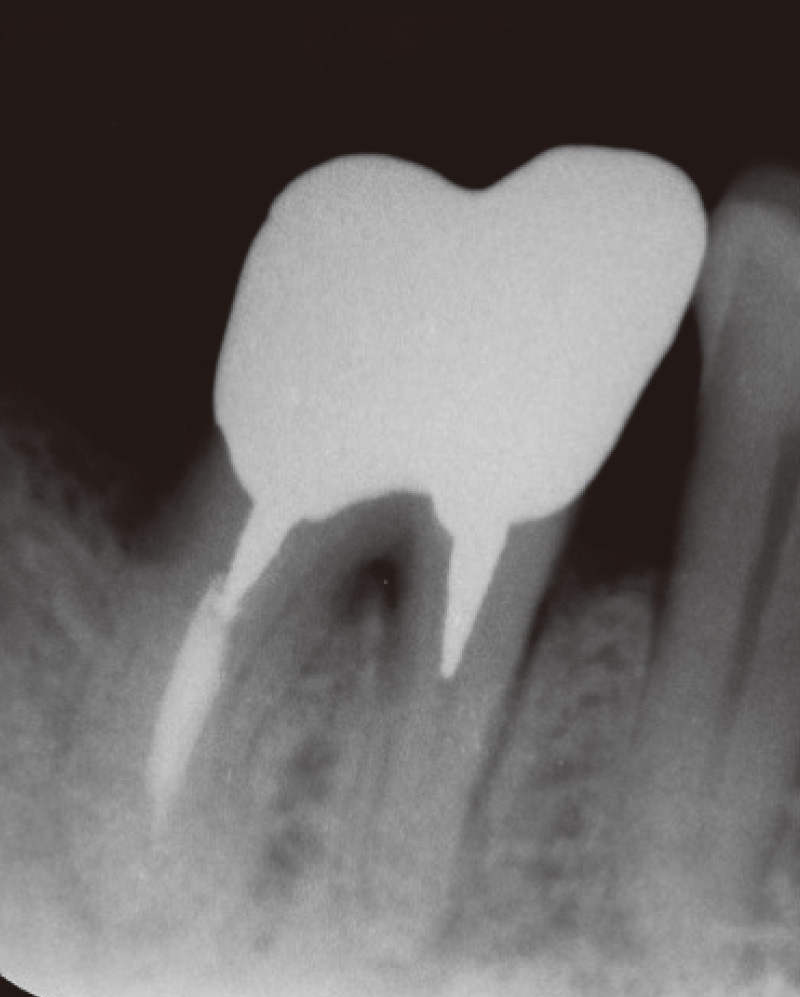

![[写真] 初診時](/academic/dentalmagazine/wp-content/uploads/sites/2/2025/11/195-3_photo10.jpg)